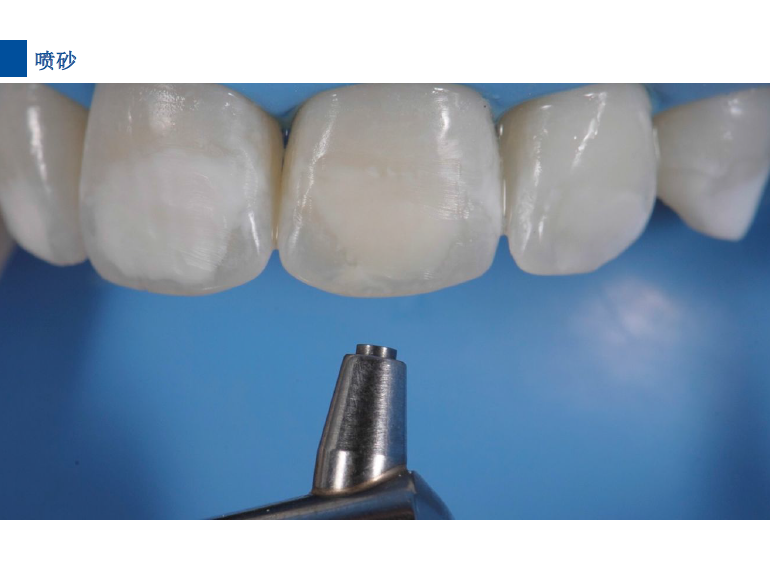

6、将配套唇颊面龋损治疗的注射头装在含爱康渗透树脂Icon-Infiltrant注射器上。

7、旋转注射器柄部将足量材料涂布于已被酸蚀的龋损表面之上,等待3分钟,并用棉球去除多余材料。不要在牙椅照明灯直射下在前牙唇面涂布树脂。)

8、光照40秒

9、将一新的注射头装在含爱康渗透树脂Icon-Infiltrant的注射器上,重复步骤7-8.等待1分钟,光照40秒。